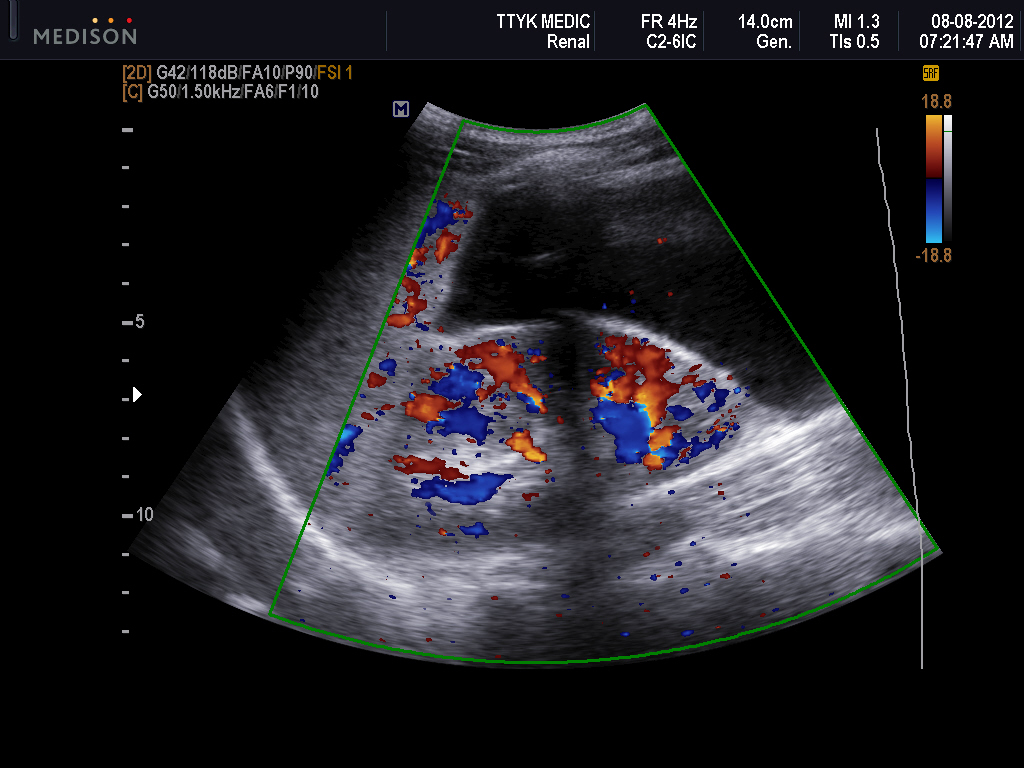

A Gallery of HighResolution, Ultrasound, Color Doppler

Fetal death was due to intrauterine death in eight cases, therapeutic abortion in eight cases and spontaneous abortion in two cases. Color doppler may show no obvious internal flow which can be distinguished from hemangioma (figure 3). The loculations range in size but in 85% of cases are as large or larger than the. This is a report of a case of cystic hygroma of the neck in a female child.

Develop strategies for inclusive, culturally safe care in the event of unexpected findings. Ultrasound is considered as being the first level study to investigate a suspected mass suggestive of cystic hygroma. Fetal cystic hygroma is a congenital malformation of the lymphatic system. Cystic hygroma of the neck:

Deliver clear and transparent communication across the continuum of healthcare professionals. Ultrasound findings favor cystic hygroma.